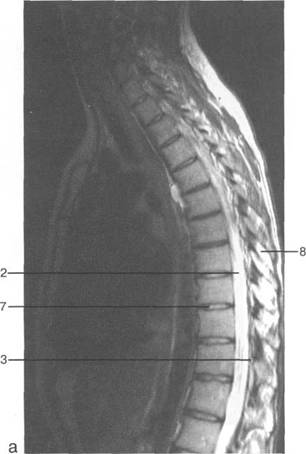

conus medullaris) LIU.

S:; Ln-Lm.

ThvlI1 LIV. (vasa corona).

ThXI1;

Lv-S,.

Lv; S,; S;; Lv.

LIV; L^; Lv; LIV;

ThK-Thx.

Thlx; Thlx;